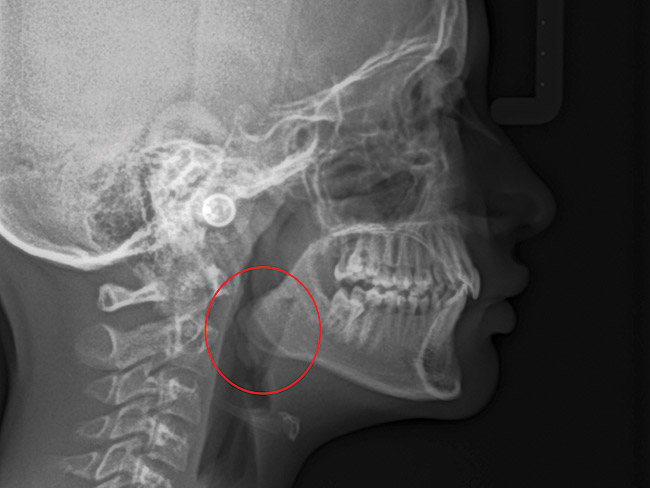

(15.) Cephalometric evaluation demonstrates significant tonsillar blockage of the airway and bimaxillary retursion.

Figure 15